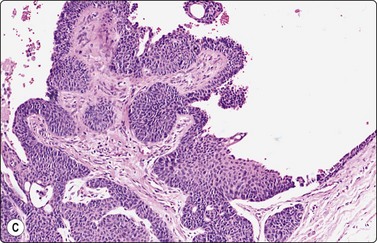

Basal cell carcinoma (Fig. 14.14)8,45-48

Criteria for diagnosis

Tight cell aggregates with sharp outline, smooth edges, often budding,

Palisading of nuclei along the edge of aggregates,

Small cells with scanty cyanophilic cytoplasm; indistinct cell borders,

Small, hyperchromatic, ovoid, overlapping nuclei; indistinct nucleoli,

Stromal material variable.

Most basal cell carcinomas (BCC) are diagnosed clinically. Scrape smears from the surface can provide rapid pretreatment confirmation, of particular importance if non-surgical treatment is considered. If the lesion is ulcerated, any inflammatory debris should be removed prior to vigorous scrapings.8 Non-ulcerated, deeply invasive tumors are suitable for FNB sampling using a thin 25–27-gauge needle.

The most characteristic feature of BCC in smears is the strong cohesiveness of the cells, which remain in well-defined tissue fragments of tightly packed small cells with palisading of nuclei along the edges. The fragments resemble tumor buds seen in tissue sections (Fig. 14.14A). The same pattern was seen in FNB smears from a rare case of distant metastasis to bone from of a large, deeply invasive BCC on the back of an elderly patient (Fig. 14.14B). The cells are small with very scanty cytoplasm and overlapping, ovoid, relatively uniform hyperchromatic nuclei. The chromatin is evenly distributed and nucleoli are inconspicuous. Subtyping of BCC is generally not possible, but stromal material can be prominent in smears from desmoplastic, infiltrating basal cell carcinoma, suggesting a differential diagnosis of chondroid syringoma (Fig. 14.14D).

image image image image

Fig. 14.14 Basal cell carcinoma

(A) Cohesive epithelial fragments with alternating sharp and irregular borders (H&E, IP); (B) Tissue fragments of very cohesive basaloid cells. The fragments have well-defined borders of cells with a tendency to palisading. This smear is a FNB sample from a bone deposit of metastasizing basal cell carcinoma (MGG, HP); (C) Tumor fragment of small, tightly packed cells, FNB smear (H&E, MP); (D) Basal cell carcinoma, infiltrating type; tumor fragment of closely packed small, uniform basal cells and adherent fibrillar fibrous stroma (MGG, LP).